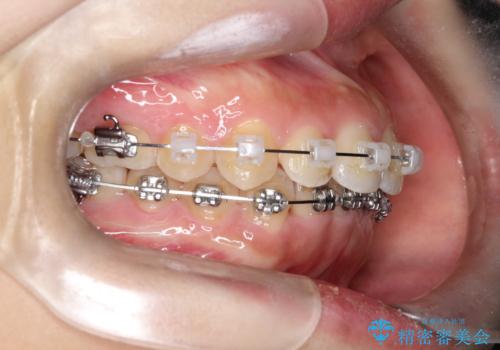

- 矯正装置

- ワイヤー装置

治療中、装置の変更を希望されたため上下で装置が異なっています。